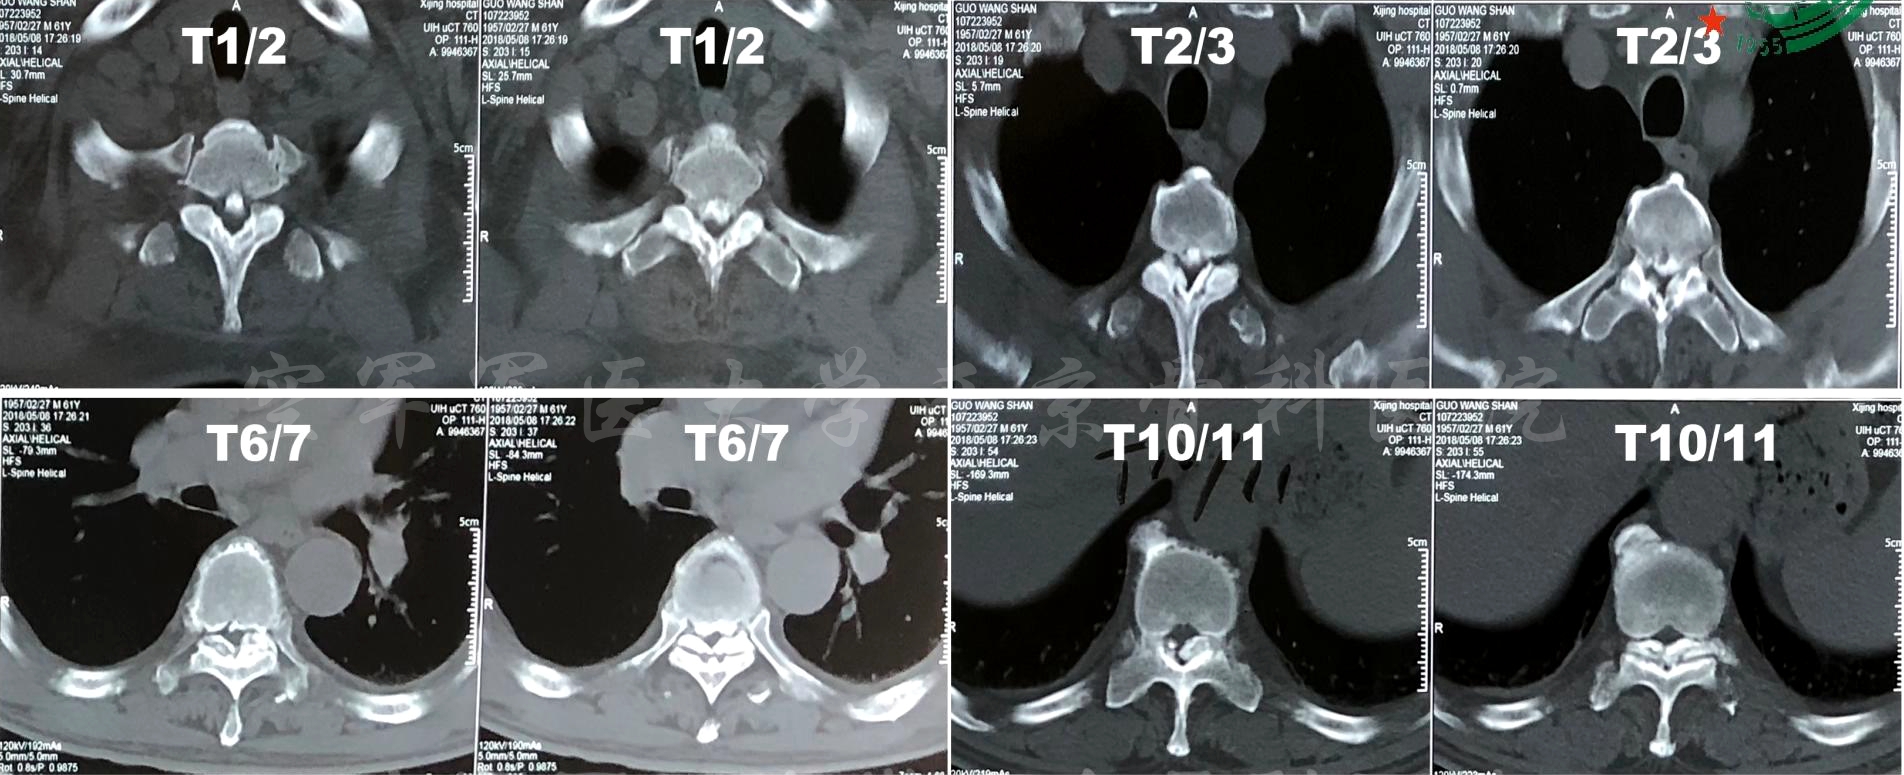

术前X线正侧位片

术前X线动力位片